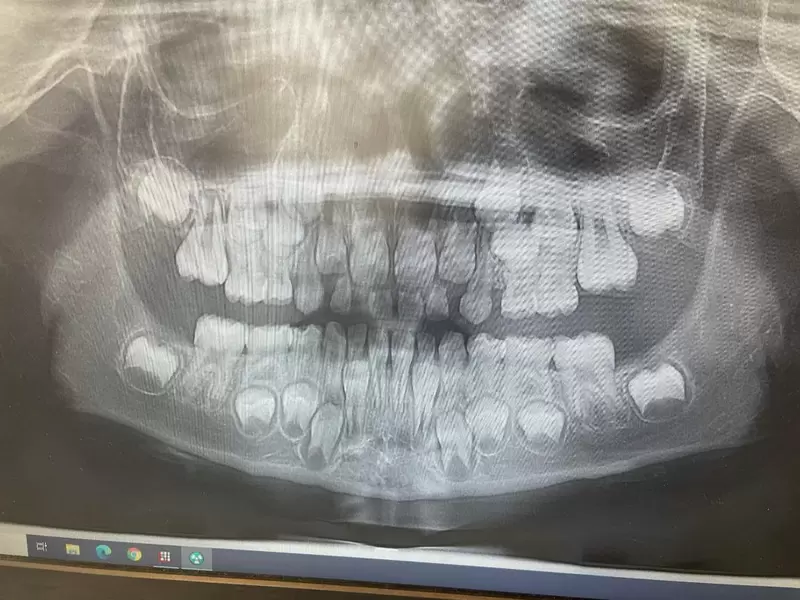

▼一個七歲孩童的牙科X光照片

圖片來自:buzzfeed